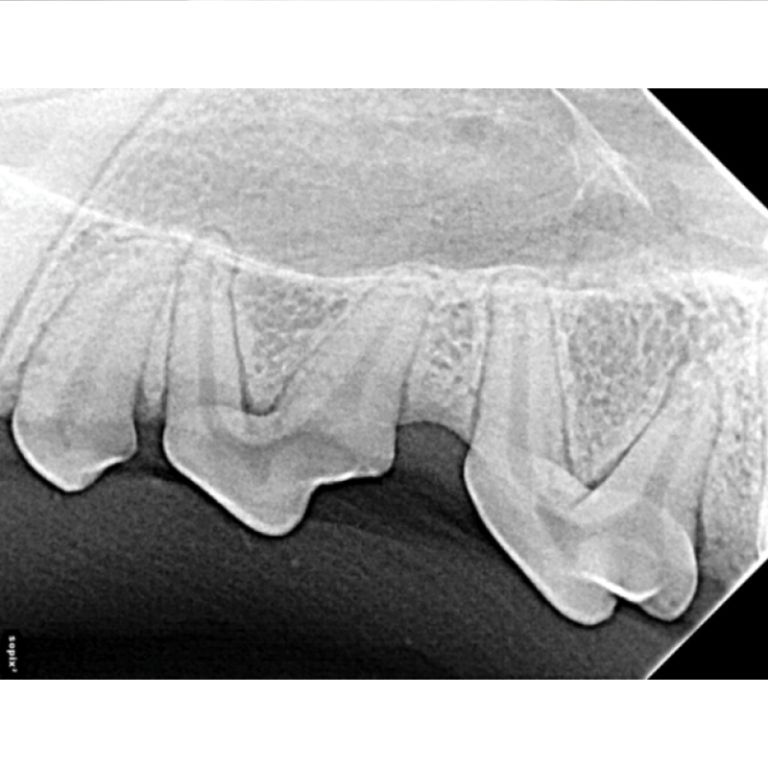

Interpretation of Dental Radiographs in Dogs and Cats, Part 2 Normal Veterinary Dental X Ray Cpd Learn what’s normal and what normal. Our wide range of veterinary dentistry courses cover everything from preventative care, dental clinics, and. Cpd online webinars allow you to further your veterinary career via distance learning. Oral radiography techniques are shown in. You’ll develop your skills, and also your confidence in making the right decisions with your small animal patients when you. Veterinary Dental X Ray Cpd.